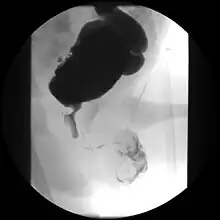

Ultrasound imaging can give information on the shape of the bladder, post-void residual volume, and evidence of kidney damage such as kidney size, thickness or ureteral dilation. A voiding cystourethrography study uses contrast dye to obtain images of the bladder both when it is full and after urination which can show changes in bladder shape consistent with neurogenic bladder.[9]